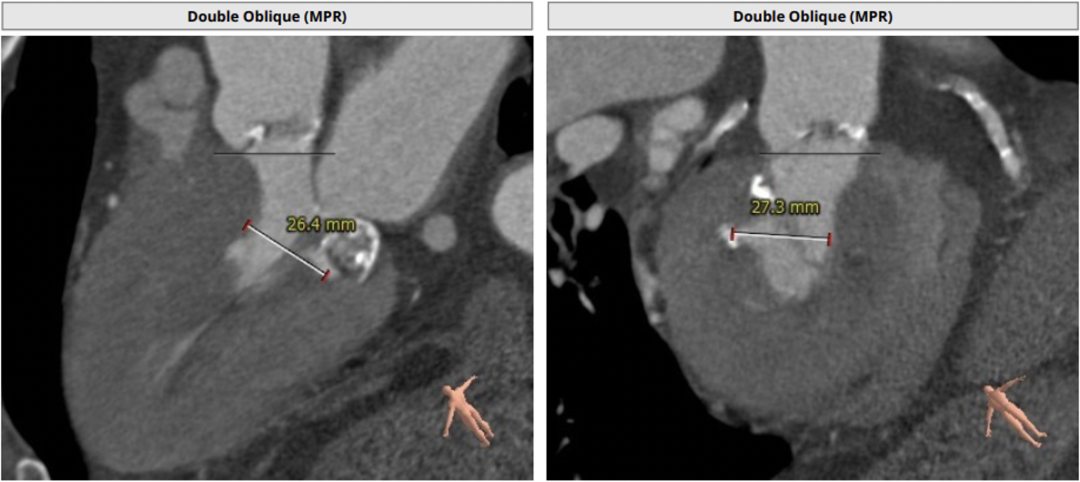

瓣环平均直径:21.8 mm,左室流出道平均直径:21.4 mm

左室小,心肌肥厚

主动脉全程可见较多斑块

CT评估显示主动脉瓣为三叶瓣,钙化积分:121.5 mm³,轻度钙化。左冠高度:15.3 mm,右冠高度:16.5 mm,冠脉高度可,法式窦结构大,左室小,心肌肥厚,升主动脉未见明显扩张。结合患者主动脉根部情况及病情等综合因素,决定使用VenusA-Plus®可回收输送系统,经由右侧股动脉入路拟植入L23型号瓣膜完成此次手术。